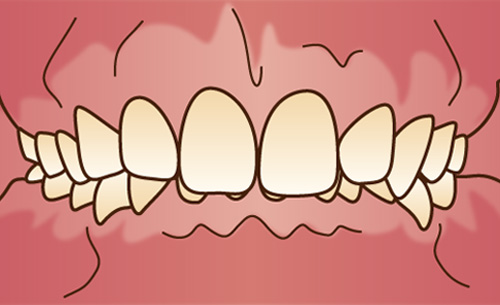

上下の歯が前に突き出ている状態で、顎の骨に問題がある場合と、歯だけが前に出ている場合とがあります。うまく噛むことができず、見た目も良くありません。唇を自然に閉じていられない場合もあります。